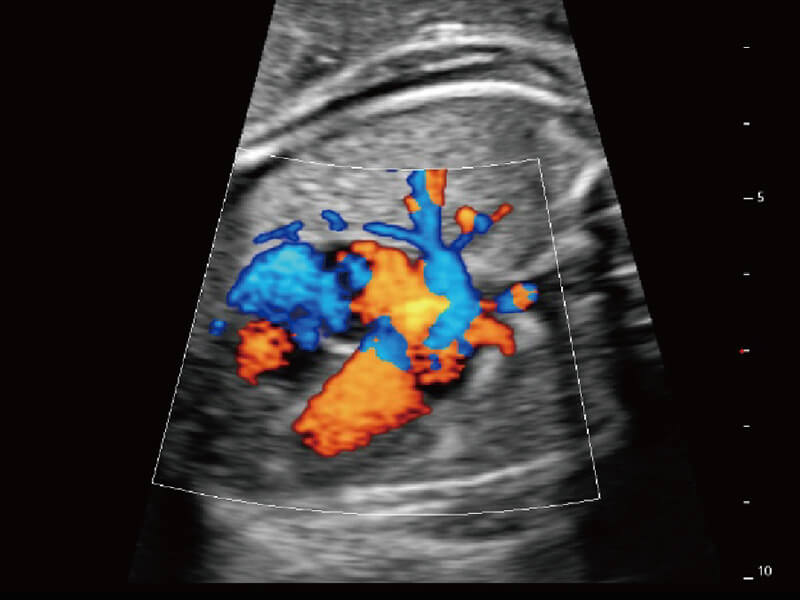

S60探头工艺,从前端信号处理每一个环节采集无损声学数据,真实还原组织原貌,再现解剖细节。

超宽频带技术,为容积成像带来优质的二维图像基础,为您呈现丰富的结构细节,栩栩如生地展示宝宝的宫内形态以及各种组织的立体结构。